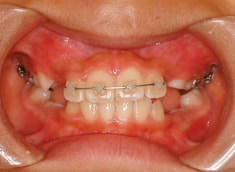

治療後(12ヶ月後)

治療開始から約3ヶ月後

治療開始後3ヶ月で、すでに前歯がジャンプしていますが、ここで注意が必要です。これは前歯の傾斜で反対咬合が一時的に解消しているだけです。ここからしっかりとフェイスマスクを使用し、上顎の牽引をしなくてはいけません。

ジャンプしただけでは「治った」ことにはなりません。今後身長と一緒に伸びてくる下顎の成長に備える必要があります。